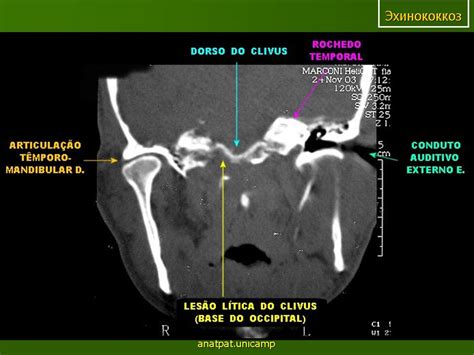

Эхинококк костей

Эхинококкоз